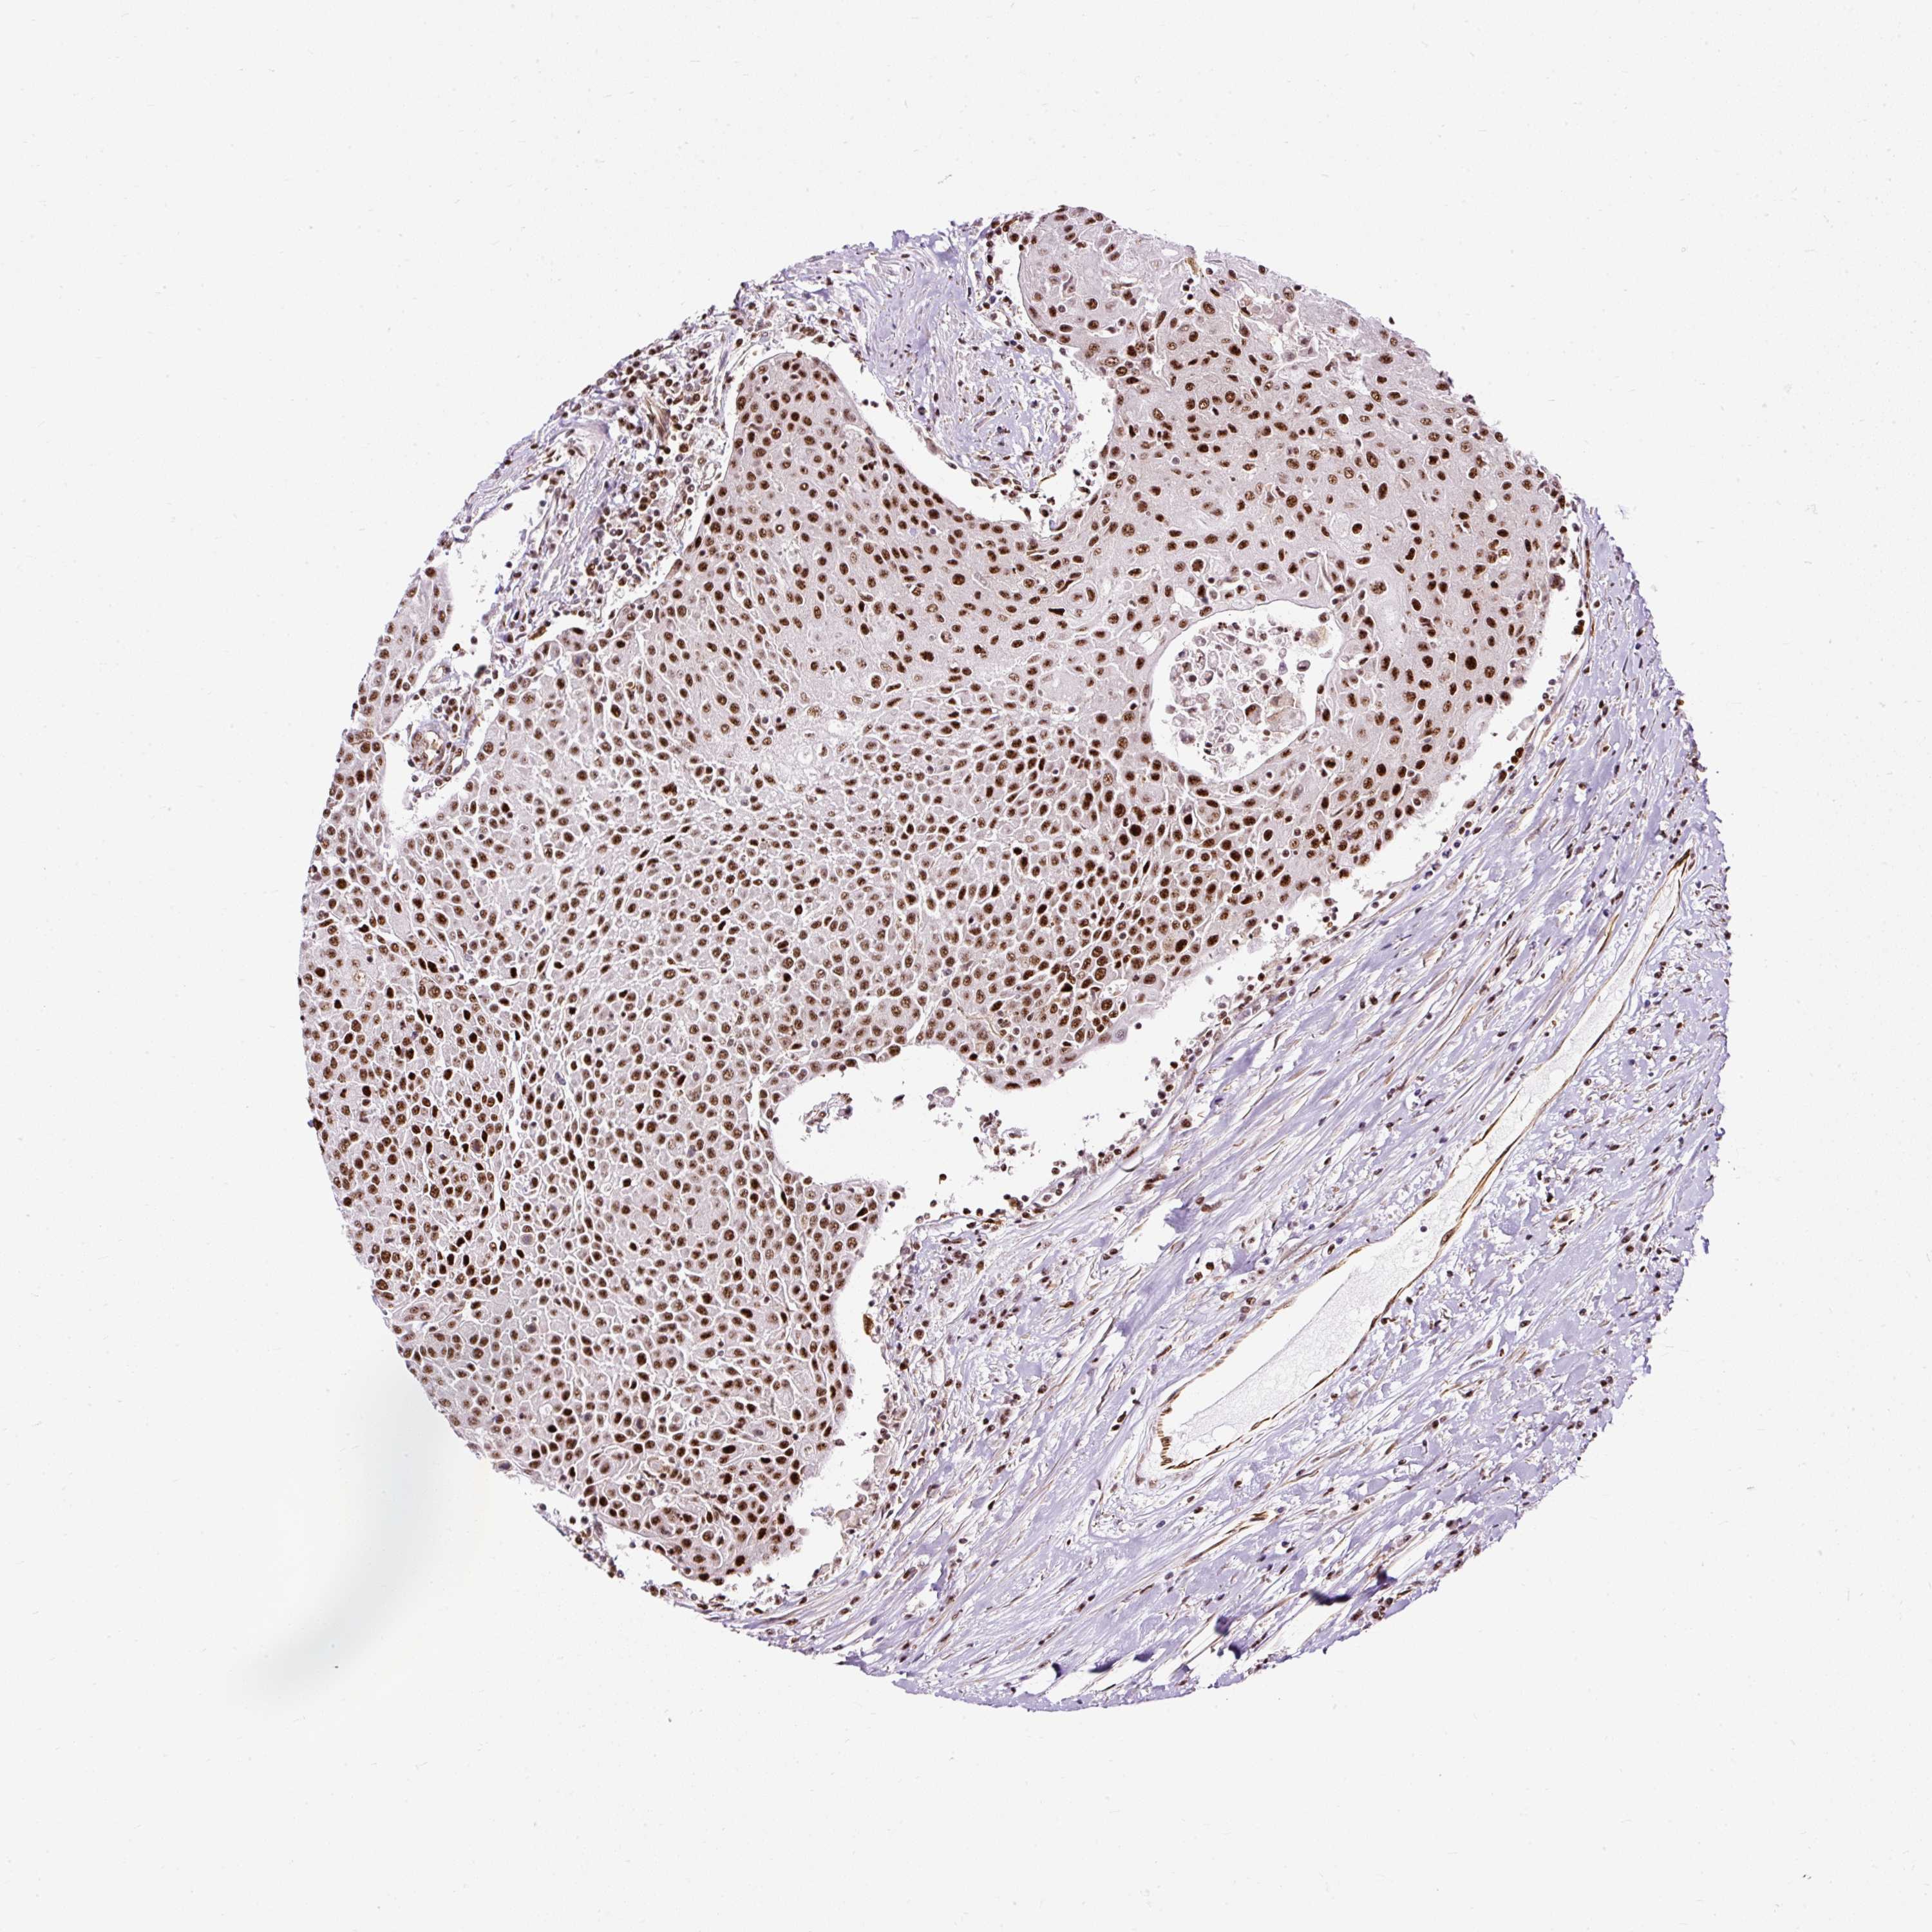

UROTHELIAL CANCER - Protein expressioni

A mouse-over function shows sample information and annotation data. Click on an image to view it in a full screen mode. Samples can be filtered based on level of antibody staining by selecting one or several of the following categories: high, medium, low and not detected. The assay and annotation is described here.

Antibody stainingi

Antibody staining in the annotated cell types in the current human tissue is reported as not detected, low, medium, or high, based on conventional immunohistochemistry profiling in selected tissues. This score is based on the combination of the staining intensity and fraction of stained cells.

Each image is clickable and will lead to virtual microscopy that enables deeper exploration of all samples and also displays staining intensity scores, fraction scores and subcellular localization as well as patient and tissue information for each sample.

Antibody HPA045663

Antibody HPA051631

Staining

High

Medium

Low

Not detected

Intensity

Strong

Moderate

Weak

Negative

Quantity

>75%

75%-25%

<25%

None

Location

Nuclear

Cytoplasmic/membranous

Cytoplasmic/membranous,nuclear

Urothelial carcinoma, High grade

Urothelial carcinoma, NOS

Urothelial carcinoma, Low grade